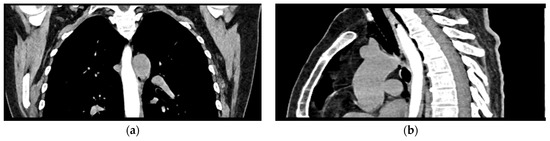

Given the patient’s history of vomiting, and consulting with the thoracic surgeon, a second CT scan with oral contrast was performed approximately 3 h later, after initial stabilization of the patient, to rule out an esophageal rupture. The subsequent imaging revealed the progression of the pneumomediastinum, with increased extension into the cervical region, including the peritracheoesophageal, perithyroidal and retropharyngeal spaces (Figure 3), without evidence of esophageal rupture (Figure 4). Oxygen therapy and empiric antibiotic therapy were initiated in the ED as initial treatments of this condition.

Figure 4.

Oral contrast chest CT scan with intact esophageal contour and no extravasation of the contrast substance: (a) coronal view; (b) sagittal view.